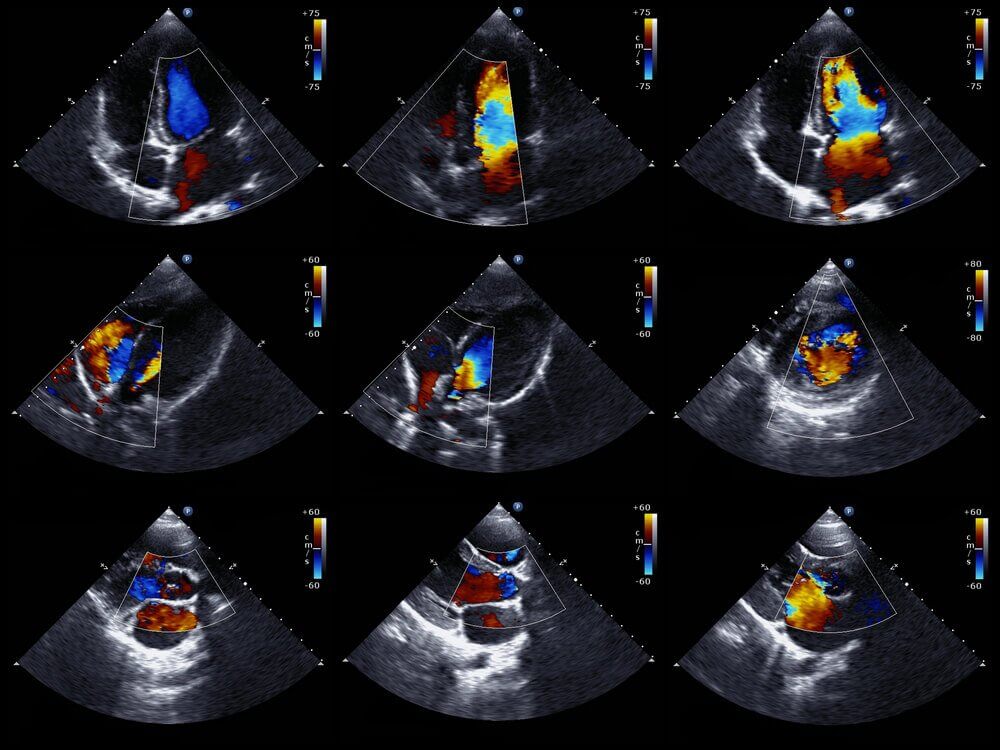

Les médecins peuvent généralement diagnostiquer cette anomalie avant la naissance du bébé. Pour cela, ils utilisent un échocardiogramme fœtal. Cette technique utilise des ondes sonores pour créer une image du cœur en mouvement.

Grâce à cela, vous pouvez voir l’apparition du cœur et examiner son fonctionnement quand les bébés sont encore dans l’utérus. Avec les informations obtenues, les médecins planifient comment traiter le bébé immédiatement après la naissance.